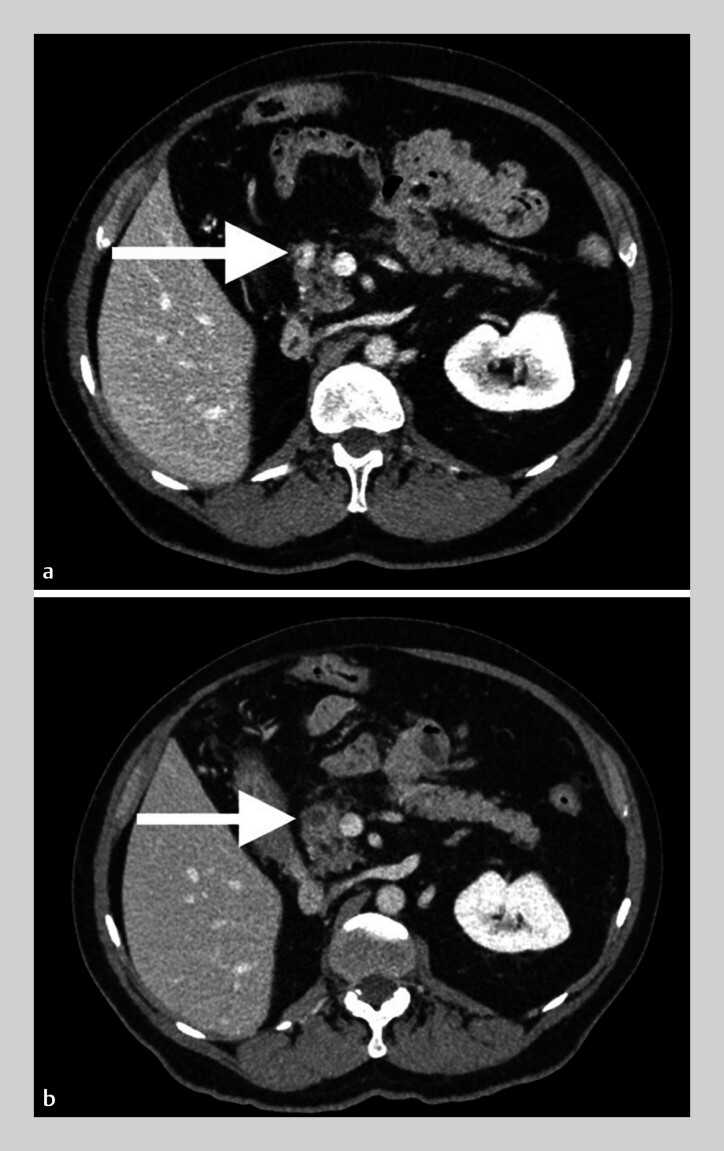

Patients and methods: This retrospective, observational study included consecutive patients referred for EUS-RFA of pancreatic RCC metastases. EUS-RFA was performed through 18G or 19G dedicated RFA needles. Effectiveness of EUS-RFA treatment was defined by necrosis with no contrast enhancement or lesion disappearance, determined by contrast-enhanced computed tomography (CT) scan, at 2 to 5 months post procedure, 1 year, and at the end of follow-up. Safety was assessed per and post procedure.

Results: Between January 2015 and January 2021, eight patients with 11 lesions were treated and median time from RCC diagnosis to pancreatic metastases RFA was 8.5 years (1-15). Mean lesion size was 13.9 mm (± 3.9). Technical success assessed by immediate post procedure contrast-enhanced CT or Doppler was 100%. At the first CT scan follow-up, complete response was 45.4% and partial response was 27.3%. At 1 year, complete response was 45.4% and partial response was 27.3%. Three patients had multiple EUS-RFAs. Adverse events occurred in 3 patients (mild acute pancreatitis, abdominal pain, and pancreatic fistula with retro-gastric pseudocyst).